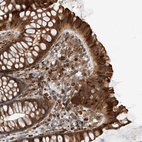

Immunohistochemical staining of human colon shows strong cytoplasmic positivity in glandular cells.